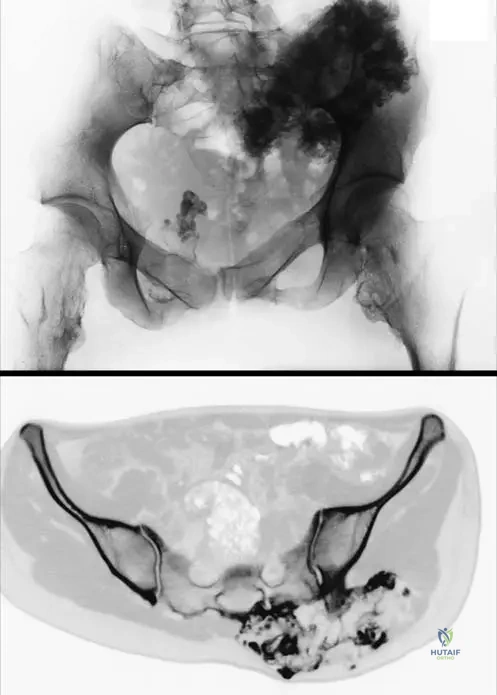

Question 52

View Answer & Explanation

Correct Answer: C

Rationale: Valgus deformities of the knee and ankle are explicitly mentioned as common deformities in patients with hereditary multiple exostoses. Osteochondromas around the knee joint can lead to malalignment of the axis, frequently resulting in genu valgum. Genu varum is less common, and the other options are not specifically highlighted as common knee deformities in HME.

A 6-year-old boy with hereditary multiple exostoses is noted to have a significant limb length discrepancy in his lower extremities, with the right leg being shorter. Radiographs show multiple osteochondromas affecting the distal femur and proximal tibia on the right. What is the underlying mechanism by which osteochondromas cause limb length discrepancies?

Correct Answer: B

Rationale: Osteochondromas arise from the growth plate (physis) and can disrupt its normal function. This disruption can lead to premature physeal closure, asymmetric growth, or general growth disturbance, resulting in limb length discrepancies and angular deformities. The other options are not the primary mechanisms for limb length discrepancy in HME.

A 16-year-old male with hereditary multiple exostoses is being evaluated for a large, firm mass on his distal femur. He reports no pain, but the mass has been slowly growing. Radiographs show a broad-based osteochondroma. What is the typical location of osteochondromas in patients with HME?

Rationale: The text explicitly states that osteochondromas in HME are "mainly at the metaphyses of long bones at the extremities." This is their characteristic location, as they arise from aberrant growth plate cartilage. They are rarely found in the diaphysis, epiphysis, articular cartilage, or bone marrow. Fig. 1.51 also shows large tibial, fibular, and femoral osteochondromas consistent with metaphyseal involvement.